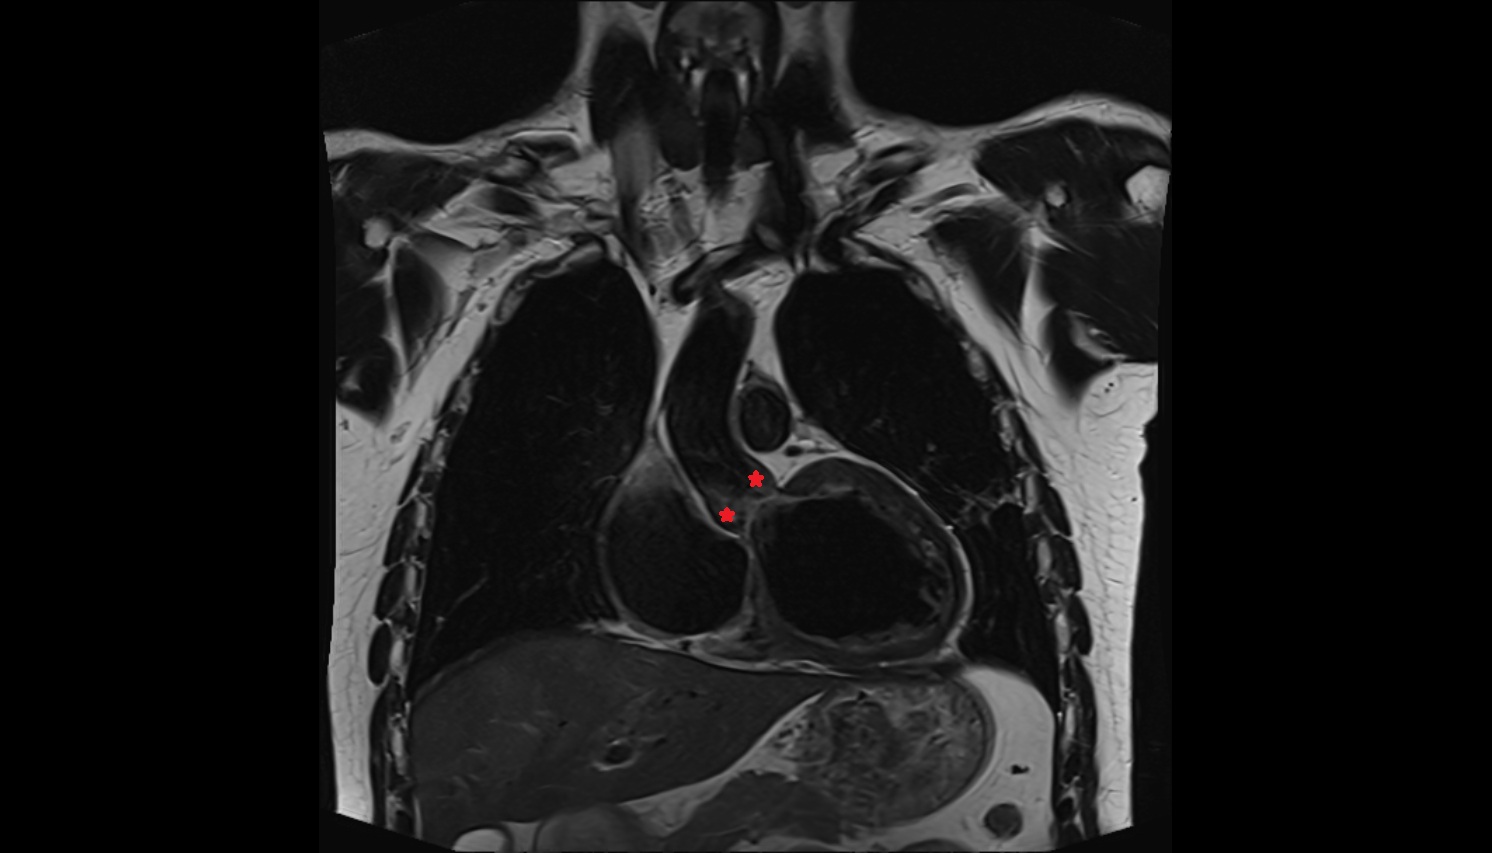

- Heart

- Left ventricle

- Left atrium

- Right ventricle

- Pulmonary trunk

- Ascending aorta

- Arch of aorta